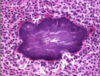

Normal bronchioles

Smooth muscle hypertrophy - inflamed bronchioles